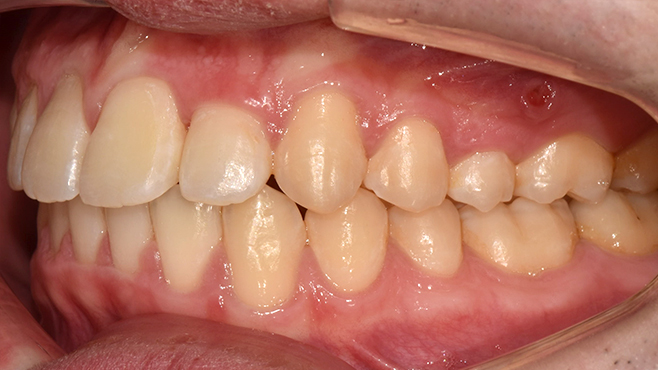

맞는 건 괜찮은데… 충치는 못 참겠습니다|20대 격투기 선수 치과 방문기

2026.02.06